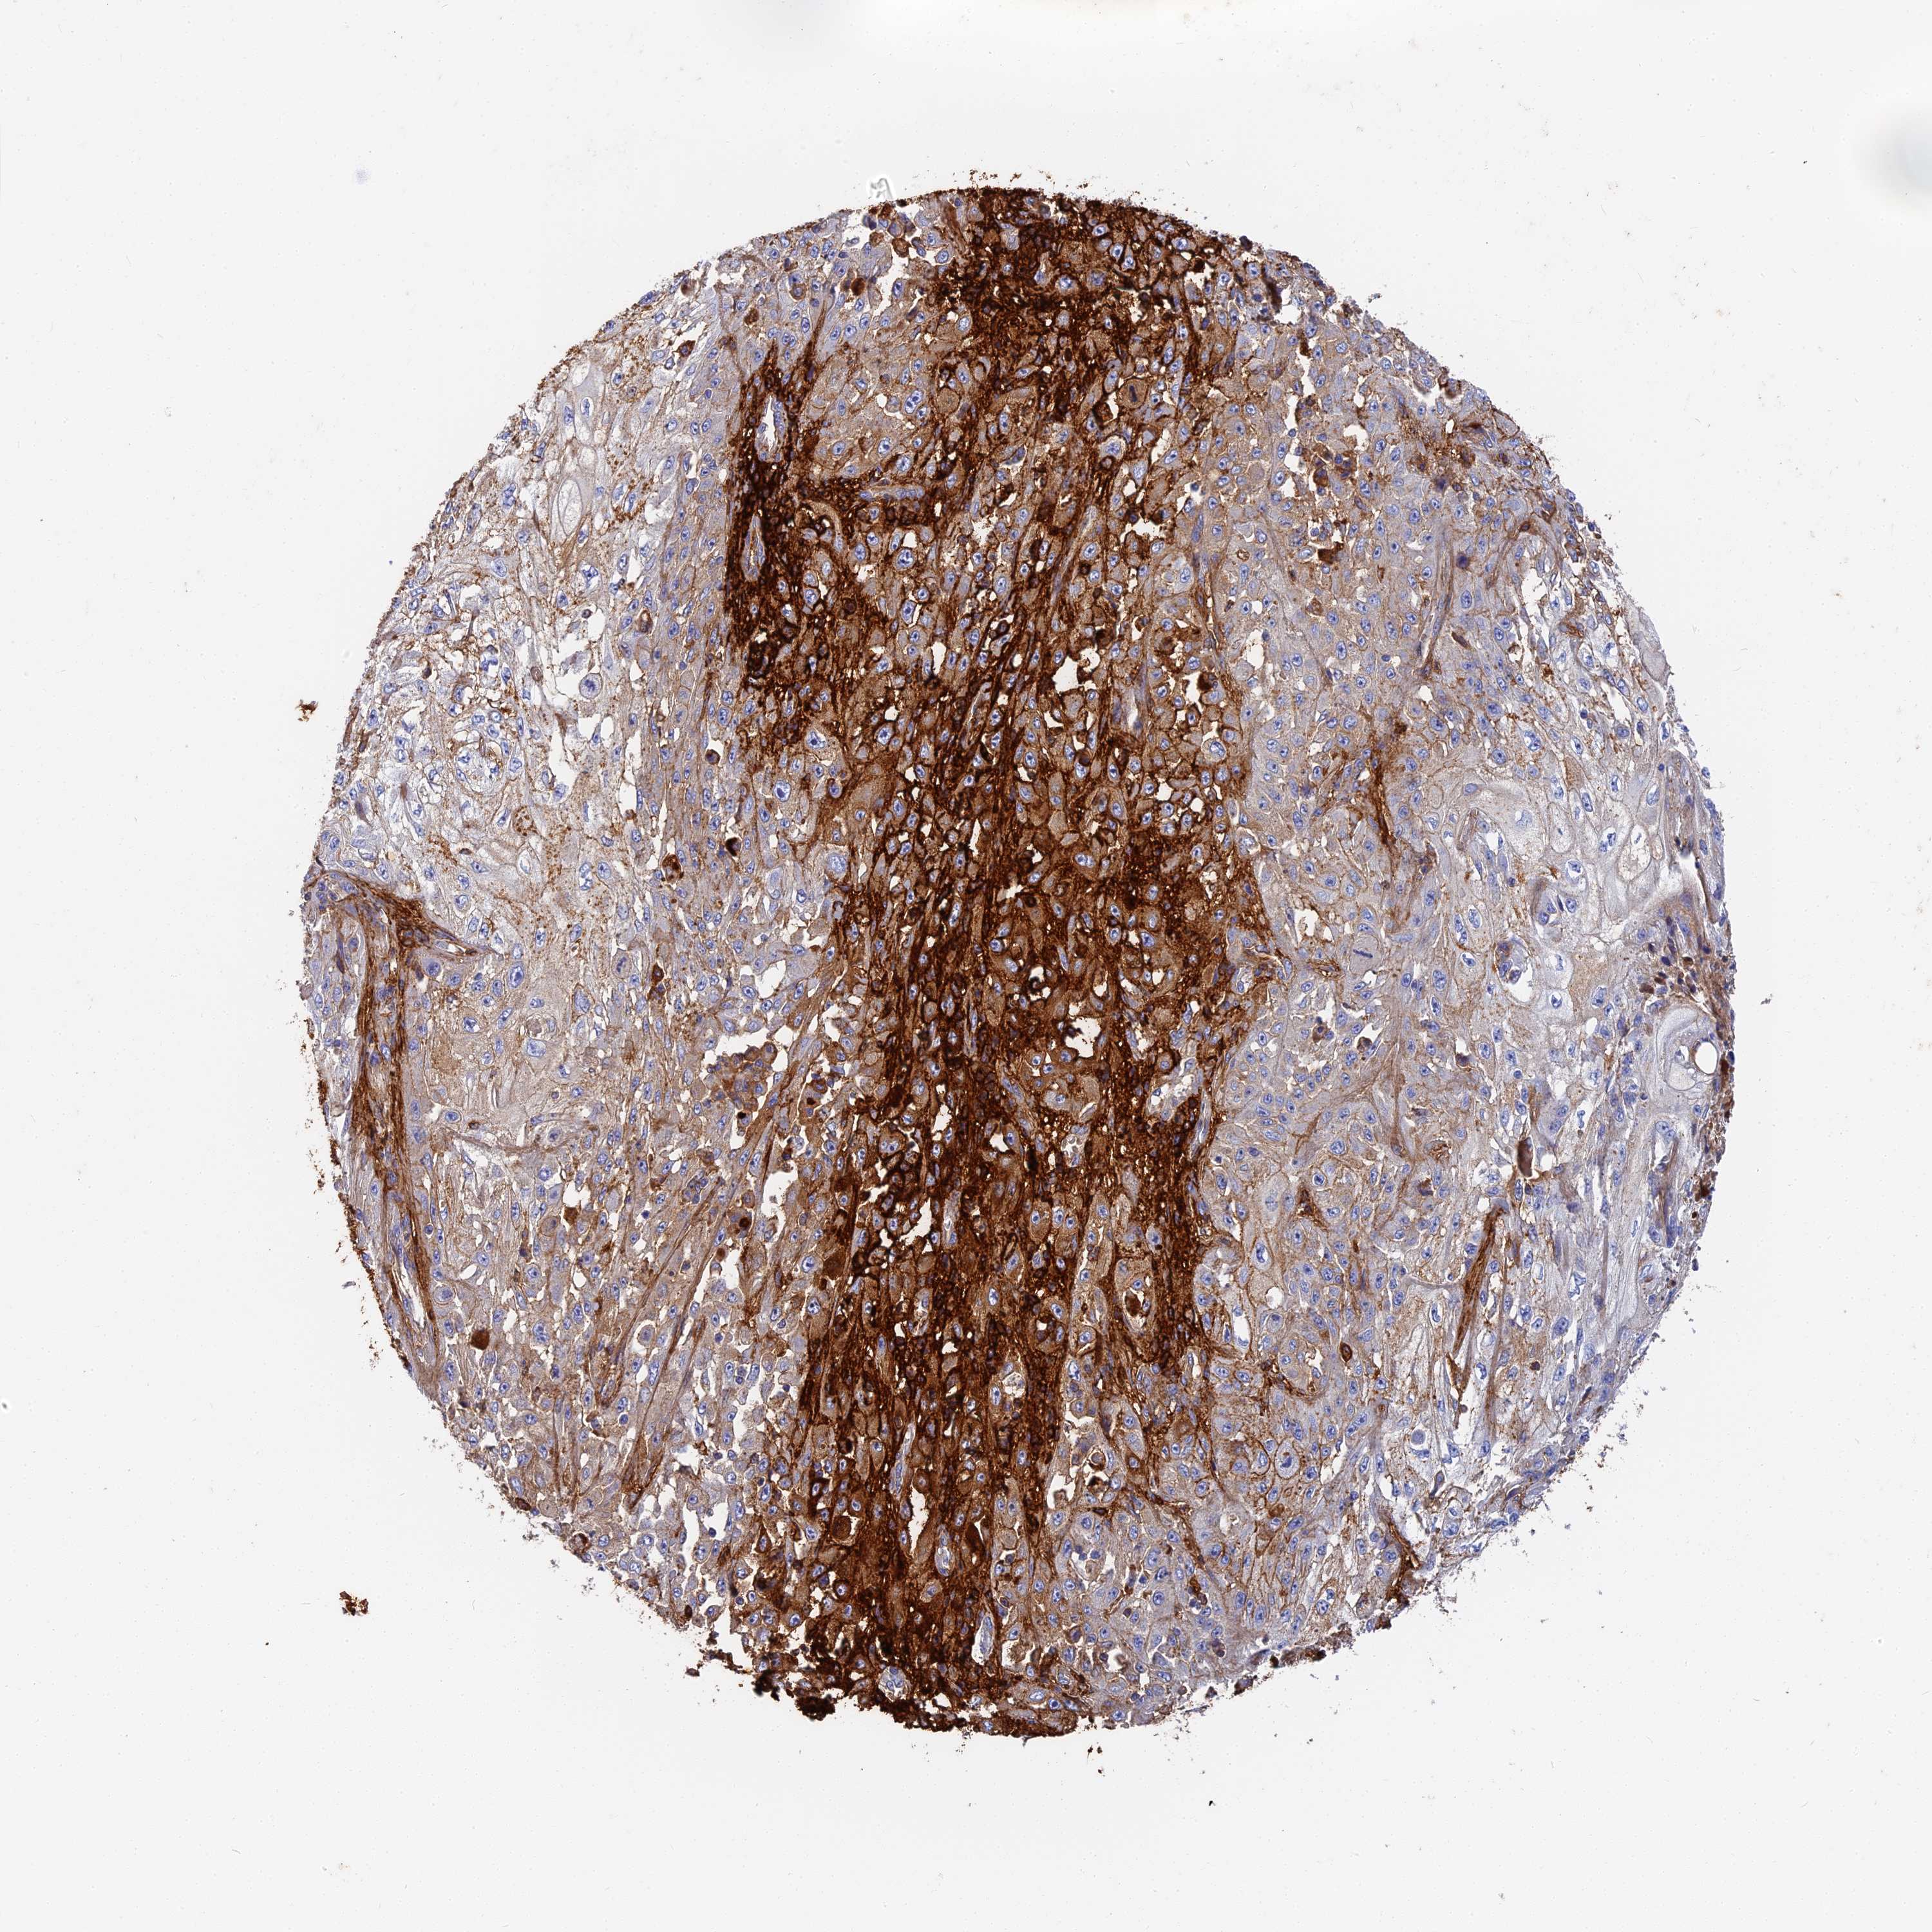

SKIN CANCER - Protein expressioni

A mouse-over function shows sample information and annotation data. Click on an image to view it in a full screen mode. Samples can be filtered based on level of antibody staining by selecting one or several of the following categories: high, medium, low and not detected. The assay and annotation is described here.

Antibody stainingi

Antibody staining in the annotated cell types in the current human tissue is reported as not detected, low, medium, or high, based on conventional immunohistochemistry profiling in selected tissues. This score is based on the combination of the staining intensity and fraction of stained cells.

Each image is clickable and will lead to virtual microscopy that enables deeper exploration of all samples and also displays staining intensity scores, fraction scores and subcellular localization as well as patient and tissue information for each sample.

Antibody HPA041639

Antibody HPA042049

Basal cell carcinoma

Squamous cell carcinoma, NOS